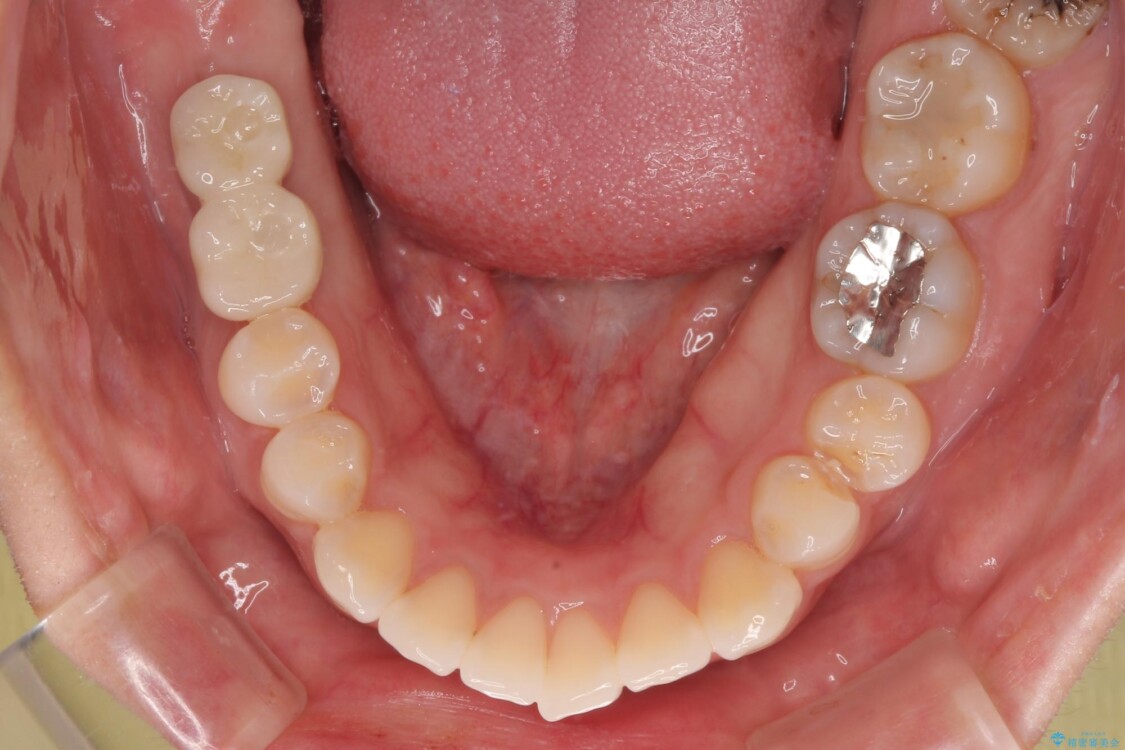

スペースが整った段階で、右下の第一大臼歯と第二大臼歯にインプラントを埋入。

治療前

• 挺出歯を圧下してスペースを確保!目立たない部分矯正で下顎大臼歯にインプラント治療を実現 治療前画像